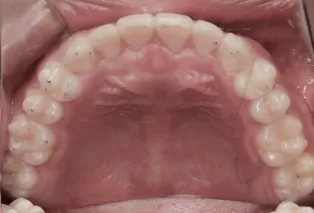

Intraoral photos after treatment